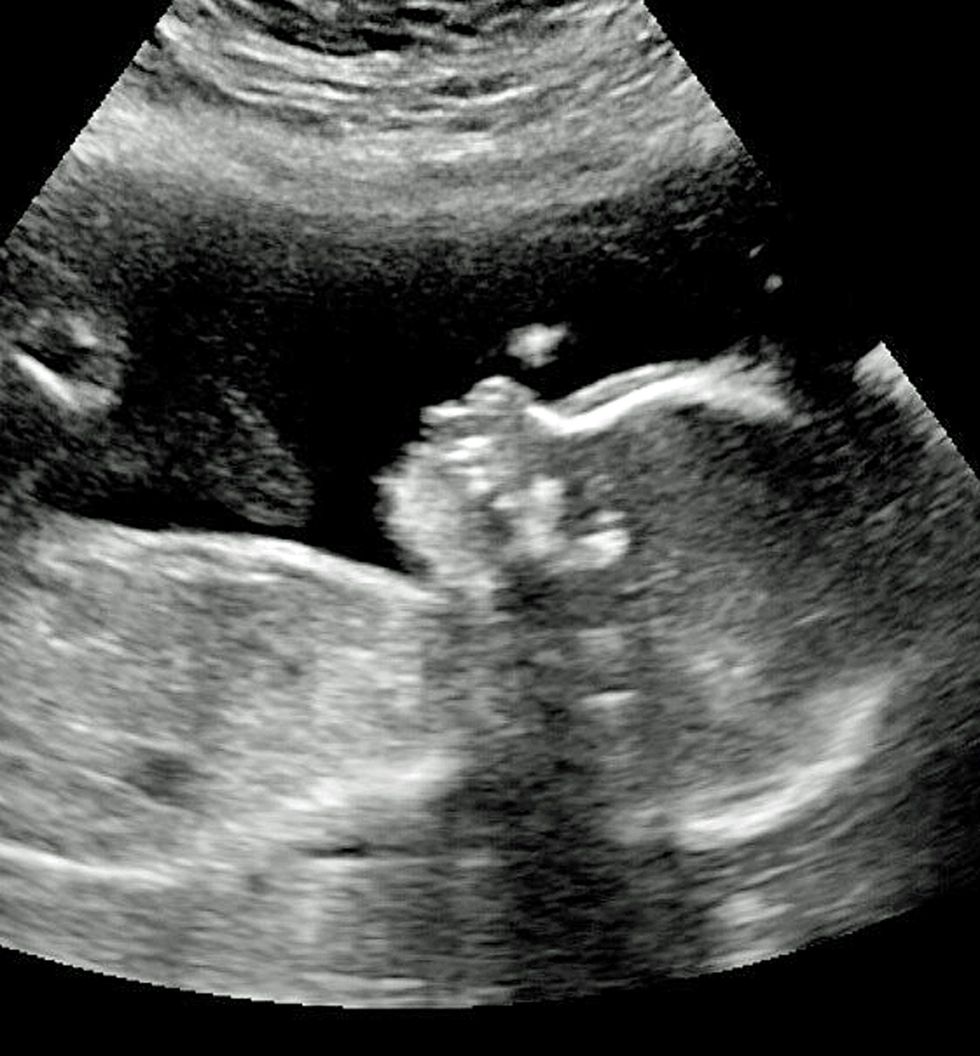

Flokët e gjatë të bebes u panë edhe në fotografinë me ultrazë (Foto)

Oliver Dunn nga Idaho e Shteteve të Bashkuara, ka pasur flokë të gjatë edhe para lindjes dhe ato janë shfaqur në imazhin me rreze X.

Për këtë familjarët kanë kuptuar gjatë shtatzënësisë, kur mjeku ka thënë se ai ka flokë shumë të gjatë. /Telegrafi/